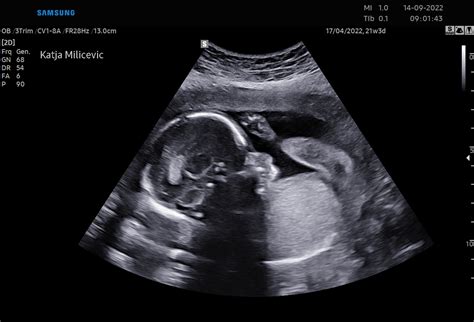

- teden je uradni konec prvega trimesečja. Tveganje za splav, ki je najvišje v prvih 12 tednih (skupaj približno 15-20 %, a veliko nižje, ko to točko presežete), se znatno zmanjša. Za mnoge ženske to prinese čustveno olajšanje. To je tudi čas za "12-tedenski pregled" - pomemben ultrazvok, pri katerem zdravnik preveri razvoj otroka, potrdi datum in preveri morebitne nepravilnosti.

Drugo trimesečje (14. do 26. teden): Na tej stopnji je lahko vaš apetit enak kot pred nosečnostjo ali pa se rahlo poveča. Lahko se zgodi tudi, da se boste sredi noči zbudili lačni. Pred spanjem kaj malega pojejte, kot je jogurt ali nekaj žitnih kosmičev. Nosečnica čuti naval energije in povečan apetit. Maternica sega nad sramnico. Na ultrazvočnem pregledu lahko vidimo, da plod sesa palec. Lahko začuti močno svetlobo od zunaj, stisne pest, se refleksno smeji. V tem obdobju je pridobitev teže do 15. tedna v povprečju 2,3 kg. Srce prečrpa za 20 % več krvi kot izven nosečnosti. Telo se pripravlja za ovulacijo, jajčna celica je pripravljena za srečanje s semenčico. Jajčna celica in semenčica se srečata in novo življenje je nastalo! Že v tem trenutku je določeno ali bo plod deklica ali deček. Zarodek se ugnezdi v zadebeljeno maternično steno in ob tem lahko nastane ugnezditvena krvavitev. Plod: srček začne utripati in ga je možno že videti z ultrazvočno preiskavo. Plodek je velikosti sezamovega zrna. Nosečnica: zaradi rasti hormona nosečnosti beta HCG-a se stopnjuje slabost. Nosečnica: ena od treh nosečnic opazi krvavitev v prvem trimestru, ki je večinoma nenevarna. Običajno je v obliki krvavkastega izcedka, lahko je tudi močna. Plod: dolg je od 14 do 20 mm in težek 1 g. Nosečnica: srčni utrip je povišan, krvni pritisk pogosto znižan. Plod: je velik 3.1 cm in težek 4 g. Ledvice, jetra, pljuča, že funkcionirajo ampak se bodo razvijali in dozorevali celo nosečnost. Plod: je velikosti fige, dolg 4.1 cm in težak 7 g. Od 11. do 20. tedna se bo teža povečala 30x in dolžina 3x. V pljuča plod vnaša majhne količine plodovnice, kar mu pomaga pri razvoju pljuč. Ušesa so že postavljena na svoje mesto. Začnejo se tudi ciklusi spanja na 5 do 10 minut. Nosečnica: slabosti, vrtoglavica, zaprtje. Plod: je velikosti slive, dolg 6.1 cm in težek 14 g. Plodovo srce deluje kot pri odraslem. Nosečnica: maternica je velikosti grenivke in telo nosečnice se počasi spreminja. Imuniteta pade, kar je naraven odgovor na nosečnost, ker bi sicer telo napadlo »vsiljivca«, ki raste v maternici. Plod: je velikosti breskve, dolg 7.4 cm in težak do 23 g. Glavica zajema še vedno polovico dolžine ploda, vendar okončine hitro rastejo in do 20. Nosečnica: pojenjajo jutranje slabosti, pogosto se pojavi zgaga. Nosečnica takrat običajno pove svoji družini in prijateljem veselo novico. Pregledi v drugem trimestru: ultrazvočni pregled morfologije ploda v 20. tednu, analize krvne slike in urina, test na toxoplazmoin test na nosečnostno sladkorno bolezen med 20. in 24. Plod: je dolg 8.3 cm in težak do 43 g. Začnejo rasti lasje, obrvi in trepalnice. Celo telo pokrijejo nežni, tanki lasje (lanugo), ki ščitijo kožo ploda in izginejo par tednov pred porodom. Nosečnica: tveganje za spontani splav se zniža za 75 %. Nosečnica čuti naval energije in povečan apetit. Maternica sega nad sramnico. Plod: je velikosti jabolka, dolžine 12.7 cm in teže 57 g. Na ultrazvočnem pregledu lahko vidimo, da sesa palec. Lahko začuti močno svetlobo od zunaj, stisne pest, se refleksno smeji. Nosečnica: nosečniški trebušček je že lepo viden. Pridobitev teže je do 15. tedna v povprečju 2,3 kg. Srce prečrpa za 20 % več krvi kot izven nosečnosti. Plod: je velikosti avokada, dolg 13.5 cm in težak 70 g. Vse mišice in kosti ploda so formirane. Izločanje urina in krvni obtok že deluje. Nosečnica: lahko že začuti nežne gibe ploda, še posebej, če se posteljica nahaja na zadnji steni maternice in če je nosečnica že rodila. Plod: je velikosti hruške, dolg 14.5 cm in težak 110 g. Ušesa so popolnoma formirana, razvija se čutilo sluha. Začne se kopičiti maščevje v telesu. Če je plod deklica se v njenih jajčnikih nahaja 6 000 000 jajčnih celic. Nosečnica: maternica potiska črevesje navzgor in na levo in desno stran. Plod je velikosti manjše artičoke, dolg 13 cm in težak 140 g. Srček je že popolnoma formiran, plod sliši srčni utrip svoje mame in zvoke iz zunanjega sveta. Nosečnica: če nosečnica že čuti gibe otroka, je normalno, da gibov ne čuti vsak dan, zato ni razloga za zaskrbljenost. Plod: je velikosti manga, dolg 17.8 cm in težak 200 g. V tem tednu se razvija verniks (beli, mastni, sirasti premaz), ki ščiti plod. Vsa čutila se intenzivno razvijajo. Nosečnica: pri teh tednih se lahko pojavi bolečina krožne vezi, ki podpira maternico. Bolečina nastane zaradi rasti maternice in je popolnoma normalna. Lahko se pojavi ob sunkovitem gibu (npr. Plod: je velikosti banane, poprečne dolžine 19.7 cm in teže 260 g. Notranji organi so že na svojem mestu kot pri odraslem, zato je čas za morfologijo oziroma ultrazvočno oceno pravilnega razvoja ploda. Nosečnica: polovica nosečnosti je že mimo! Velikost maternice je do popka. Plod: je povprečne dolžine 21.6 cm in teže 340 g. Požira plodovnico, kar pomaga razvoju prebavil. Je obdobje intenzivnega gibanja ploda, ki ga nosečnica čuti na vseh straneh trebuha. Plod: je dolg 25 cm in težek 400 g. Zdaj že sliši zelo dobro, ker so kosti notranjega ušesa že dovolj razvite. Nosečnica: zaradi visokih vrednosti hormonov, v nosečnosti lasje postanejo močnejši in gostejši, nohti so trdi in močni. Vrh maternice je 2 cm nad popkom. Plod: je velikosti jajčevca, dolžine 28 cm in teža 450 g. V plodovi koži nastaja pigment zaradi katerega ni več prozorna temveč postaja roza/ rdeče barve. V pljučih ploda se razvijajo krvne žile. Plod vse bolj razlikuje zvoke, zato lahko reagira na glasbo in že lahko prepozna mamin glas. Nosečnica: zaradi zadrževanja tekočine v telesu in pritiska maternice, ki raste, na žile v mali medenici, pogosto začnejo zatekati noge. Plod: je dolg 30 cm in težak 540 g. Oči ploda reagirajo na svetlobo, nozdrvi se odpirajo, refleksi so bolj izraziti. V telesu ploda se proizvajajo bele krvne celice, možgani se intenzivno razvijajo. V pljučih se začne proizvajanje sluzi, tako imenovanega surfaktanta, ki omogoča, da se zračni mehurčki napolnijo z zrakom ne da bi se zlepili. Nosečnica: med 24. in 28. tednom se lahko pojavi nosečnostna sladkorna bolezen, zato na pregledu v 24. tednu nosečnica dobi napotnico za obremenitveni test z glukozo, ki ga opravi do 28. tedna. Plod: je dolg 35 cm in težek 600-700 g. Že lahko pokaže katero roko bo bolj uporabljal. Lahko »vdihuje« in »izdihuje« plodovnico in če je pogoltne preveč, kolca. Nosečnica: maternica je že nad popkom, pritisk na želodec se stopnjuje, kot tudi zgaga. Sluh je že tako razvit, da lahko plod skoči, če sliši glasen zvok. Možgani so gladki in še vedno ni razvite povezave med živčnimi celicami. Je še vedno dovolj prostora, da plod lahko hitro spreminja položaj v maternici. Nosečnica: veliko nosečnic začne čutiti bolečine v križu. Sklepi postanejo, zaradi delovanja hormonov, sproščeni in nekoliko bolj ohlapni, kar obremenjuje sklepne vezi. Zaradi pritiska maternice, ki raste, na trebušne organe, se lahko pojavi ostra bolečina pod rebri. Najljubša aktivnost ploda je sesanje palca. Trepalnice ploda dokončno izrastejo. Pljuča so še vedno nezrela za samostojno dihanje. Pogosto odpira oči, ki so pri vseh plodovih modre barve. Nosečnica: po drugem trimestru, času običajno čudovitega počutja, se ponovno pojavlja utrujenost. Pogosti so tudi krči v nogah, še posebej po noči.